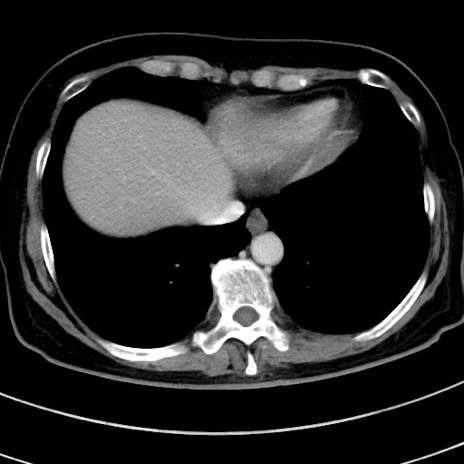

症例9(横断像)

【症例】 60歳代女性

【主訴】むかつき、みぞおちの痛み

【現病歴】3日前よりむかつきがあり、食事がとれない。

【既往歴】糖尿病

【身体所見】発熱なし、心窩部圧痛軽度あるも、腹膜刺激症状なし。

【データ】WBC 7400、CRP 1.92